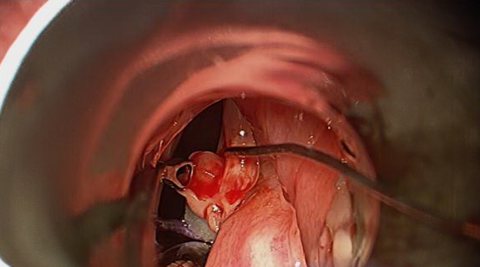

The patient elected to proceed with excision of the right vocal cord lesion with microdirect laryngoscopy under general anaesthesia (Microdirect Laryngoscopy (Suspension Microlaryngoscopy or Direct Laryngoscopy) concomitantly with endoscopic biopsy of adenoid tissue.

Intraoperative Images